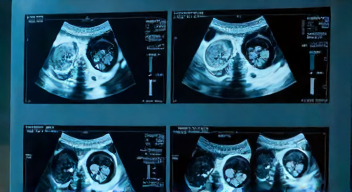

Ich heiße Roman Küppers (Fachgebiet Medizin, 47 Jahre) und ich erinnere mich an meine ersten Tage in der Notaufnahme. Der Druck war hoch. Jede Sekunde zählte. Das TEX20 Ultraschallgerät (schnelles Diagnosetool, 2023) fiel mir sofort ins Auge. Ich schaltete es ein und begann zu arbeiten ( … ) Keine langen Bootzeiten, kein Frust. Ein klarer Vorteil ( … ) 33.000 Notfälle jährlich. In solch einem Umfeld ist Zeit der entscheidende Faktor. Ich hatte sofort Zugriff auf hochqualitative Bilder. Egal, ob Herz, Abdomen oder Weichteile – das TEX20 lieferte Ergebnisse · Besonders beeindruckend war die Nadelvisualisierung. Das Gerät half mir, Katheter präzise zu platzieren. Ich fühlte mich sicher. Der große Touchscreen war intuitiv. Kein Knöpfe drücken. Bei Covid-Patienten konnte ich das Gerät schnell desinfizieren. Ein Pluspunkt – Ich war immer bereit, um zu helfen. Und ich war nicht allein » Wie handhabst du den Druck in der Notaufnahme?

Guten Tag, hier ist meine Antwort als Christoph Schmitz (Chefarzt der Zentralen Notaufnahme, 2024), und ich beantworte deine Frage: Der Druck in der Notaufnahme ist enorm. Das TEX20 hat unser Arbeitsumfeld revolutioniert. Das Gerät ist mobil, wendig und hat große Rollen. Einmal in Betrieb, kann ich sofort mit der Untersuchung beginnen. Bei 33.000 Notfällen pro Jahr ist Effizienz unerlässlich. Das Gerät ermöglicht es uns, die Bildqualität zu optimieren, sodass wir auch auf Röntgenbilder verzichten können. Wir erkennen Pneumothorax zuverlässig. Die hohe Bildqualität ist nicht nur ein Vorteil – sie ist entscheidend. Das TEX20 hat die Art und Weise, wie wir arbeiten, grundlegend verändert. Glaubst du, dass moderne Technik die Notfallmedizin weiter transformieren kann?